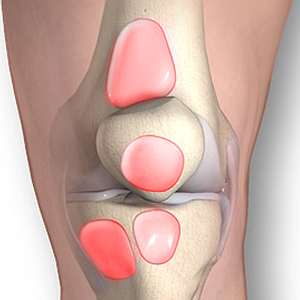

Bursitis

BURSITIS Y SINOVITIS